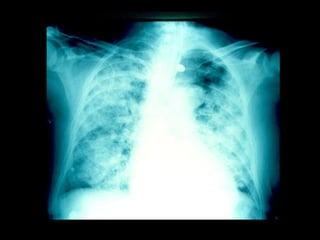

Infiltrado en alas de mariposa ó de murciélago, por edema pulmonar . Líneas B de Kerley .

Infiltrado en alasde mariposa ó de murciélago, por edema pulmonar . Líneas B de Kerley .